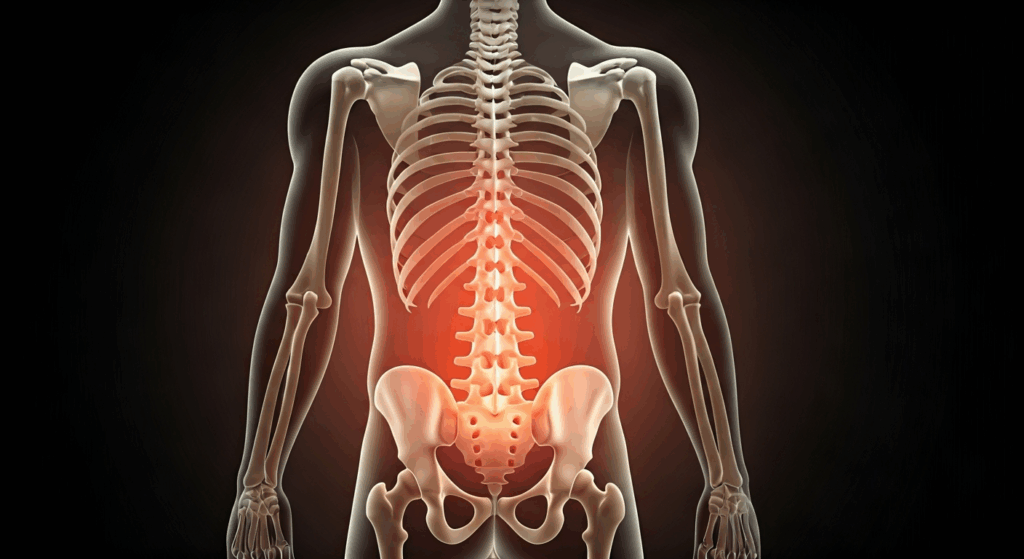

Understanding Back Pain and Its Medication Needs

Types of Back Pain Commonly Treated with Medication

Back pain, or backache, can come from things like degenerative disc disease, sudden injuries, or muscle spasms. Each kind of back pain needs a different way to get relief.